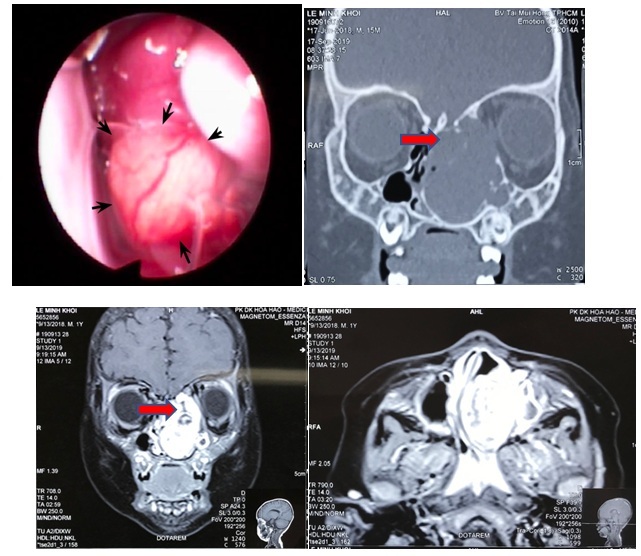

Bé trai 1 tuổi lồi mắt, nghẹt mũi hóa ra thủ phạm là khối u lớn

Bệnh nhi 15 tháng tuổi bị lồi mắt trái, nghẹt mũi trái 4 tháng, khi đến viện bác sĩ phát hiện khối u lớn chèn ép là nguyên nhân chính.